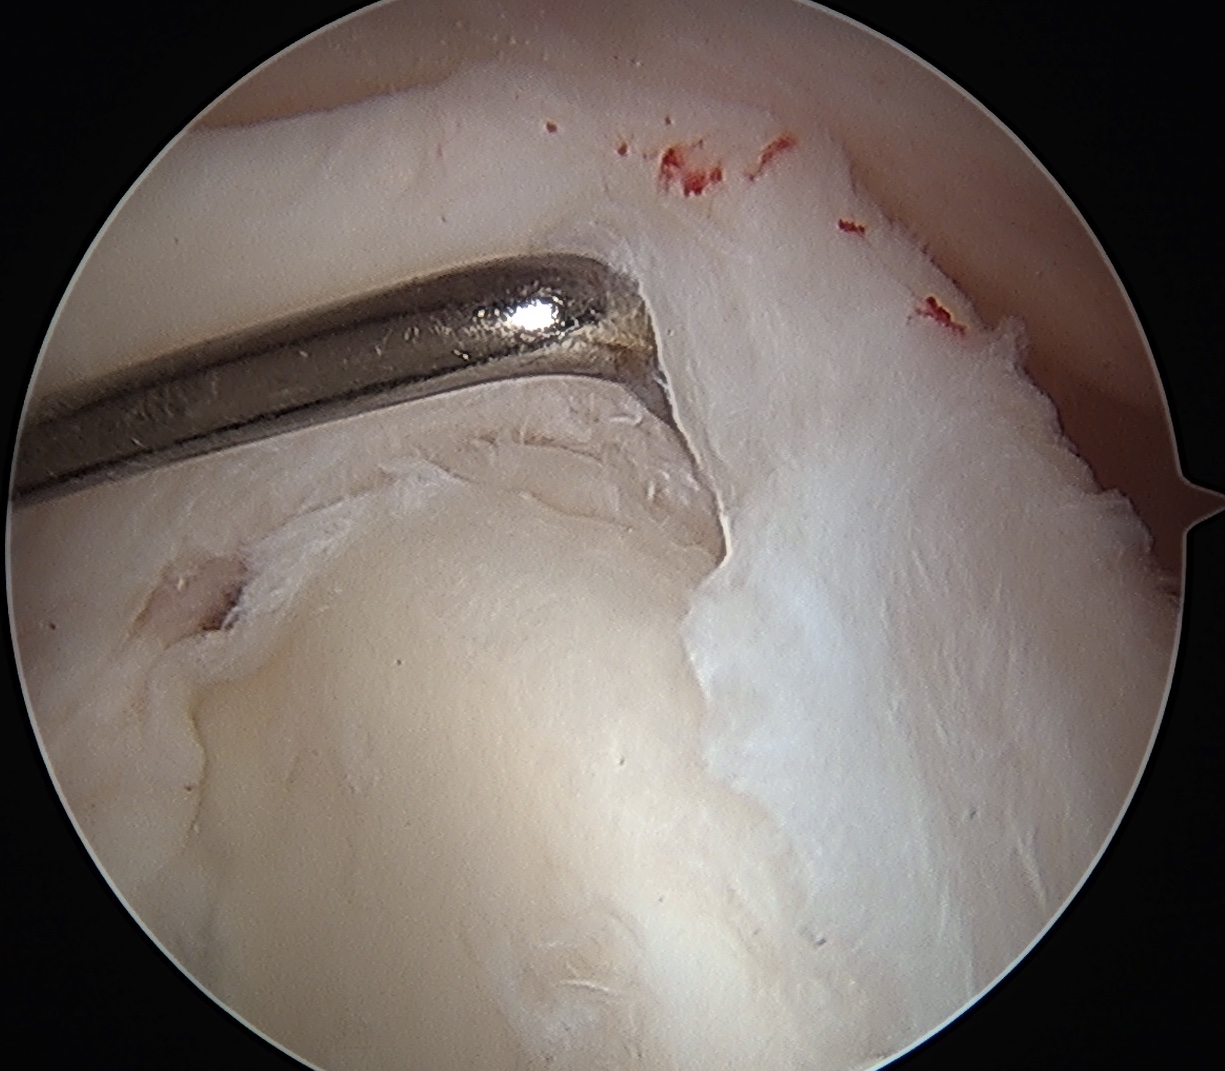

Arthroscopy

Normal insertion of superior labrum onto glenoid